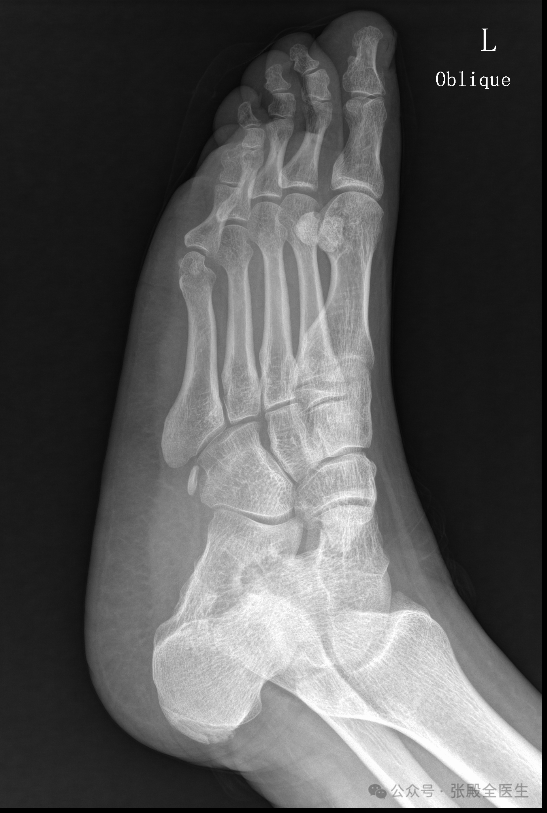

患者XX,男,35岁,左足疼痛不适半年。患者无诱因出现左足疼痛,受凉后明显,连及小腿,无力感。平素口干、口苦,时大便稀,睡眠差,诉经常喝可乐。查足X片提示:左足副舟骨。左足跟骨质增生。化验尿酸:451μmol/l。这位患者足痛部位为足背及脚趾,考虑主要为痛风性关节炎,非副舟骨导致。